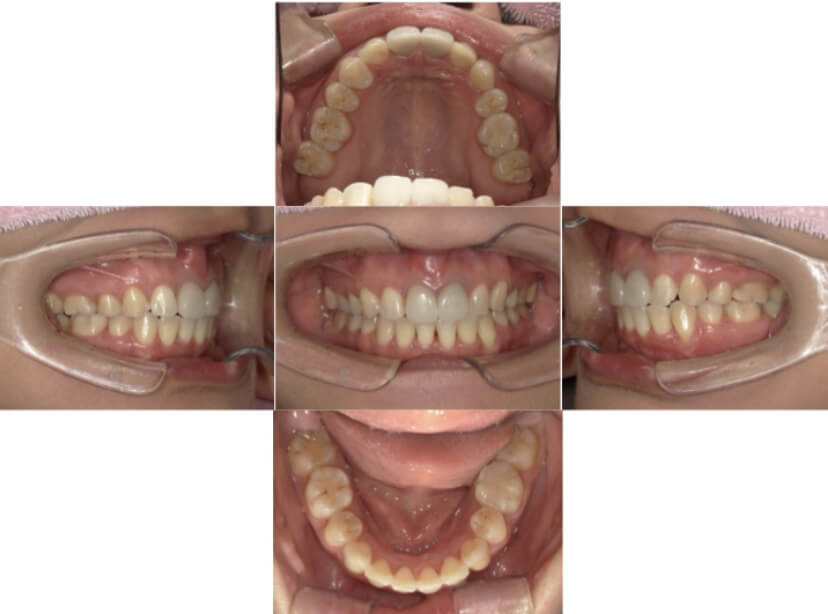

BEFORE

AFTER

上下顎叢生、上顎前突(出っ歯、上下の前歯のガタガタ)のケースです。

装置はラビアル(上下表側)で、上顎の小臼歯を2本抜歯を行っています。抜歯したスペースを使って、上の前歯の後方移動と叢生(ガタガタ)と出っ歯の改善を行っています。下は歯と歯の間にIPR(隣接面削合)を行い、スペースを確保し、叢生の改善を行っています。

主訴 前歯のガタガタと出っ歯が気になる。

年齢・性別 47歳 女性

お住まいの地域 神奈川県川崎市

治療方針 抜歯スペースおよびIPRを利用して上前歯の叢生(ガタガタ)の改善

抜歯部位 上顎左右第一小臼歯

使用装置 ラビアル(上下表側)、顎間ゴム

治療期間 2年0か月

治療回数 15回

リテーナー クリアリテーナー